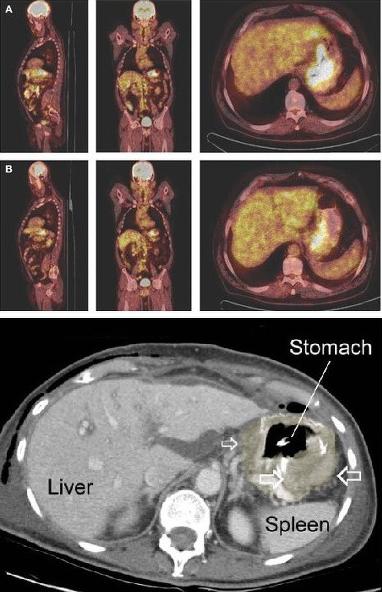

- La medecine nucleaire PET scan en

association CT scanner ( PET/CT ) pour etude scintigraphique de la

clairence de oesophage , du RGO avec les subtance

radioactif de marque 99mTc et etude le bilan

d'extention gang;lionaire et metastatique des

neoformations

PET/CT :

Cancer de estomac ( gastric melanoma ) . na pas

d'extention regional et metastasique |

Cancer de l'estoma avec extention

regionaire et metastasique du foie . Image PET scan |